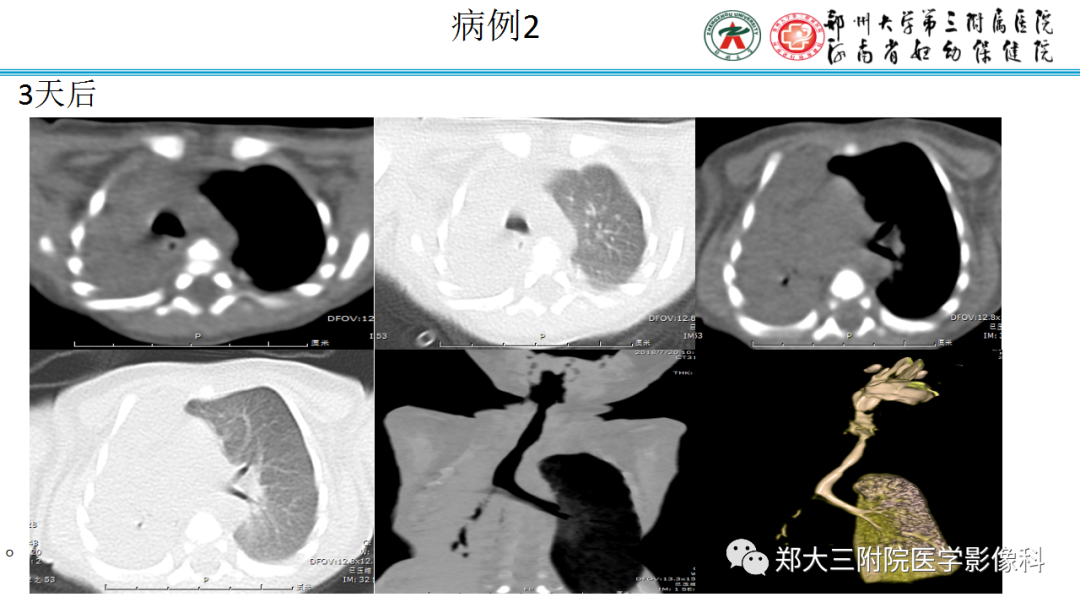

纵隔大细胞神经内分泌癌1例CT影像  张力性纵隔气肿影像表现及严重度分级

张力性纵隔气肿影像表现及严重度分级  迅速增大的肺部结节,首先考虑良性,确诊需要肺穿

迅速增大的肺部结节,首先考虑良性,确诊需要肺穿  肺隔离症:易误诊为肺癌的占位性病变,肺穿刺禁忌!